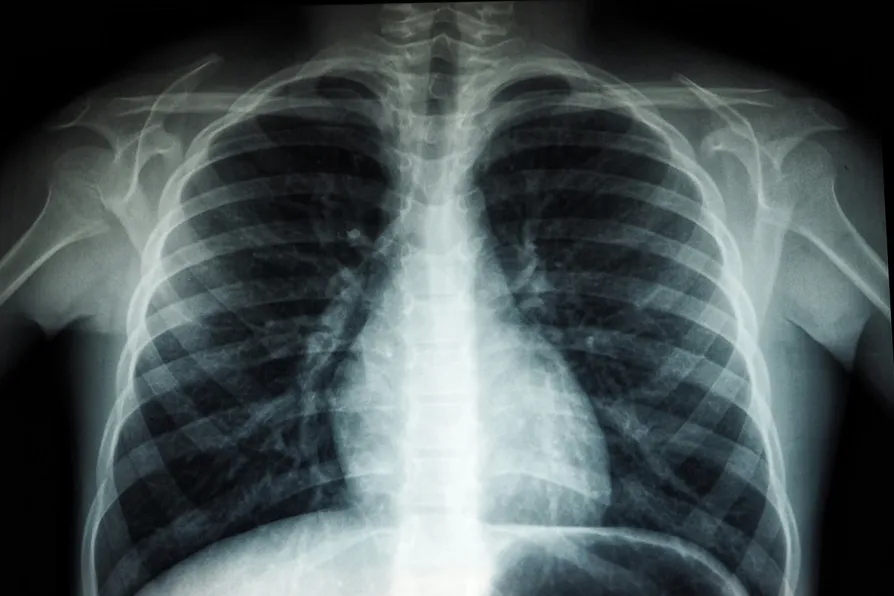

CAMPAIGNERS are demanding Scotland introduce a nationwide screening programme for lung cancer, with ministers being told action is critical.

Cancer Research UK made the plea as it revealed more than two thirds (68 per cent) of cases of lung cancer are diagnosed at a later stage when treatment is less likely to be successful.

The charity is calling on the Scottish government to immediately roll out a targeted lung-cancer screening programme in a bid to diagnose cases earlier and improve survival rates for sufferers.